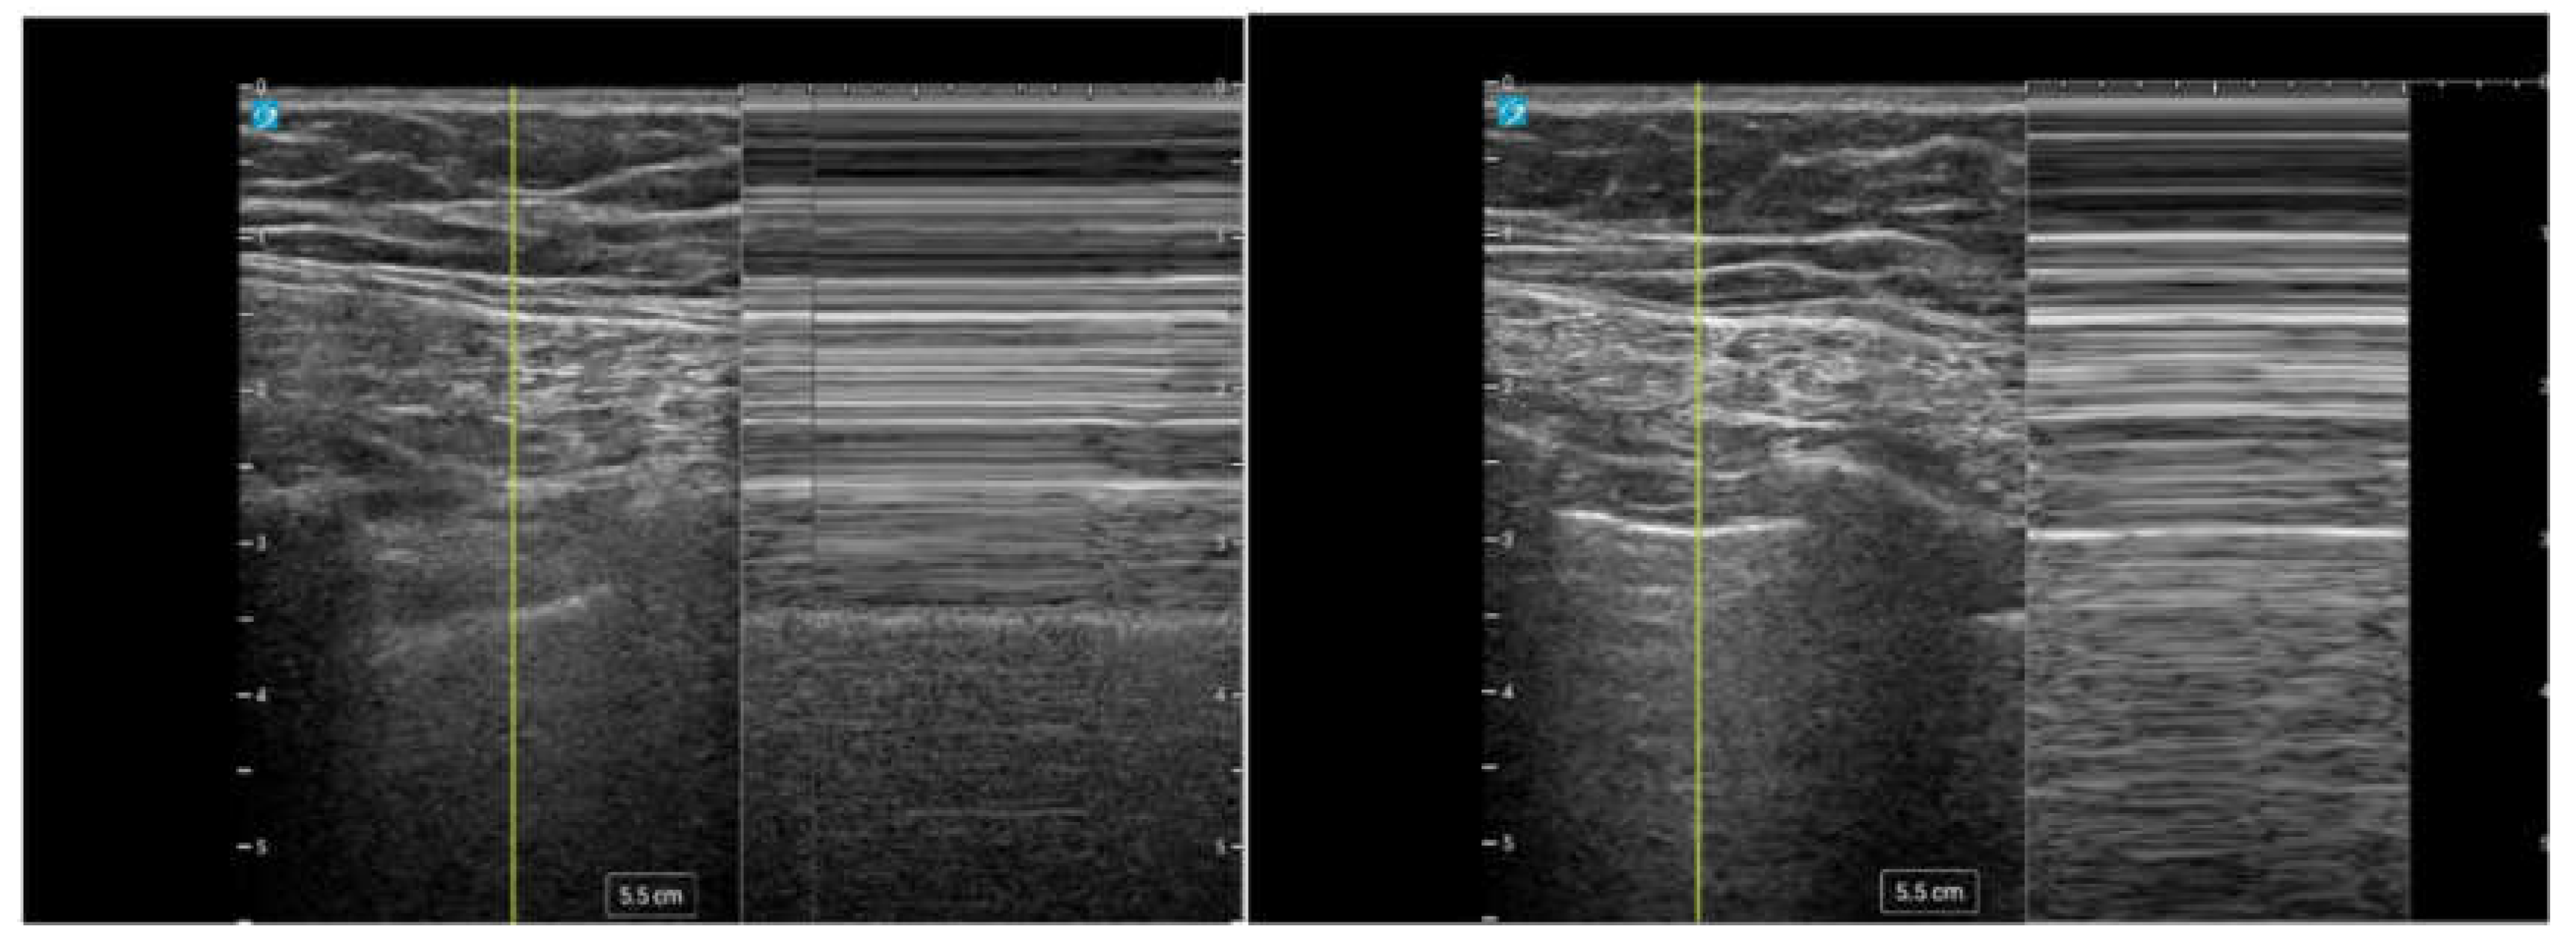

Lung Sliding

During the respiratory cycle, the visceral and parietal pleura move relative to each other. Utilizing ultrasound, this dynamic movement can be visualized as a shimmering effect along the pleural line referred to as “lung sliding.” This movement can be seen with two dimensional (2D) ultrasound (Video 1) and motion (M) mode (Figure 4) [16]. When using M mode, it is classically described as the pattern of “sandy beach” with the proximal subcutaneous tissue representing water, and the movement of the lung parenchyma representing a beach [16]. The presence of lung sliding suggests that the evaluated region is being actively ventilated with the lung parenchyma reaching the pleural line, and it significantly reduces the likelihood of pneumothorax at thatsite [10].

Figure 4. M mode demonstrating lung sliding in 2-dimensional (2D) ultrasound and Motion mode (M-mode).